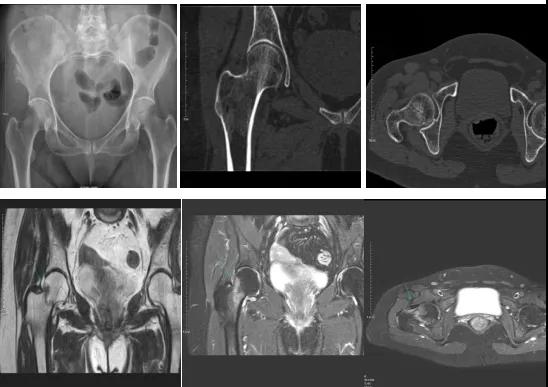

2.CT或MRI檢查。CT是斷面成像,不會(huì)出現(xiàn)重疊而導(dǎo)致漏診,同時(shí)CT還可以進(jìn)行多平面的重建,除了發(fā)現(xiàn)X線無法發(fā)現(xiàn)的骨折外,還可以三維直觀的顯示骨折的程度,對(duì)臨床治療有指導(dǎo)意義。CT無法發(fā)現(xiàn)骨裂、不全骨折或者骨挫傷,對(duì)軟組織的損傷診斷也有局限性,MRI就可以發(fā)現(xiàn)這些損傷。

DR示:右側(cè)股骨頸未見明顯骨折征象。CT右側(cè)股骨頸骨質(zhì)密度不均?;颊唧w征明顯,為明確診斷,行MRI檢查。MRI示:右側(cè)股骨頸T1WI呈低信號(hào),脂肪抑制序列呈高信號(hào);提示右側(cè)股骨頸隱匿性骨折。

隱匿性骨折是一種假隱性現(xiàn)象,CT、MRI、核素骨顯像有助于隱匿性骨折的診斷,各有優(yōu)劣,應(yīng)合理選擇。